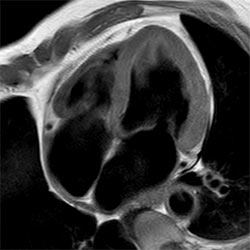

Cardiac